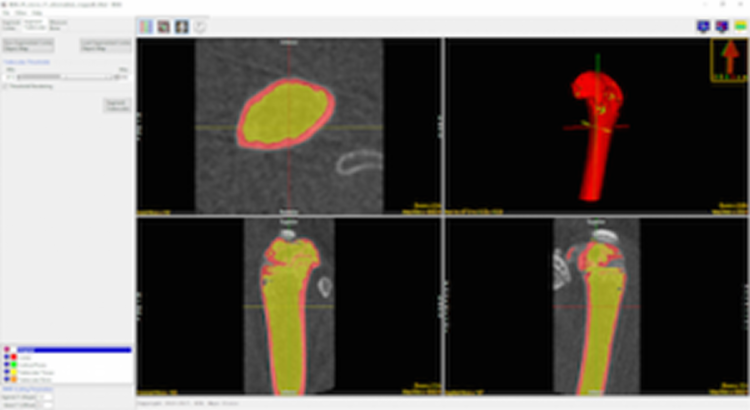

Trabecular Bone Segmentation

Upon user approval the add-on will now complete the segmentation process by identifying the trabecular bone in the trabecular region. Two new regions, the trabecular bone and intra-trabecular space will be derived.